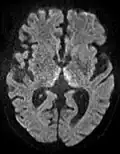

The most common application of conventional DWI (without DTI) is in acute brain ischemia. DWI directly visualizes the ischemic necrosis in cerebral infarction in the form of a cytotoxic edema,[38] appearing as a high DWI signal within minutes of arterial occlusion.[39] With perfusion MRI detecting both the infarcted core and the salvageable penumbra, the latter can be quantified by DWI and perfusion MRI.[40]

-

DWI showing necrosis (shown as brighter) in a cerebral infarction -

DWI showing restricted diffusion in the medial dorsal thalami consistent with Wernicke encephalopathy -

DWI showing cortical ribbon-like high signal consistent with diffusion restriction in a patient with known MELAS syndrome

Cerebral infarction leads to diffusion restriction, and the difference between images with various DWI weighting will therefore be minor, leading to an ADC image with low signal in the infarcted area.[24] A decreased ADC may be detected minutes after a cerebral infarction.[26] The high signal of infarcted tissue on conventional DWI is a result of its partial T2 weighting.[27]